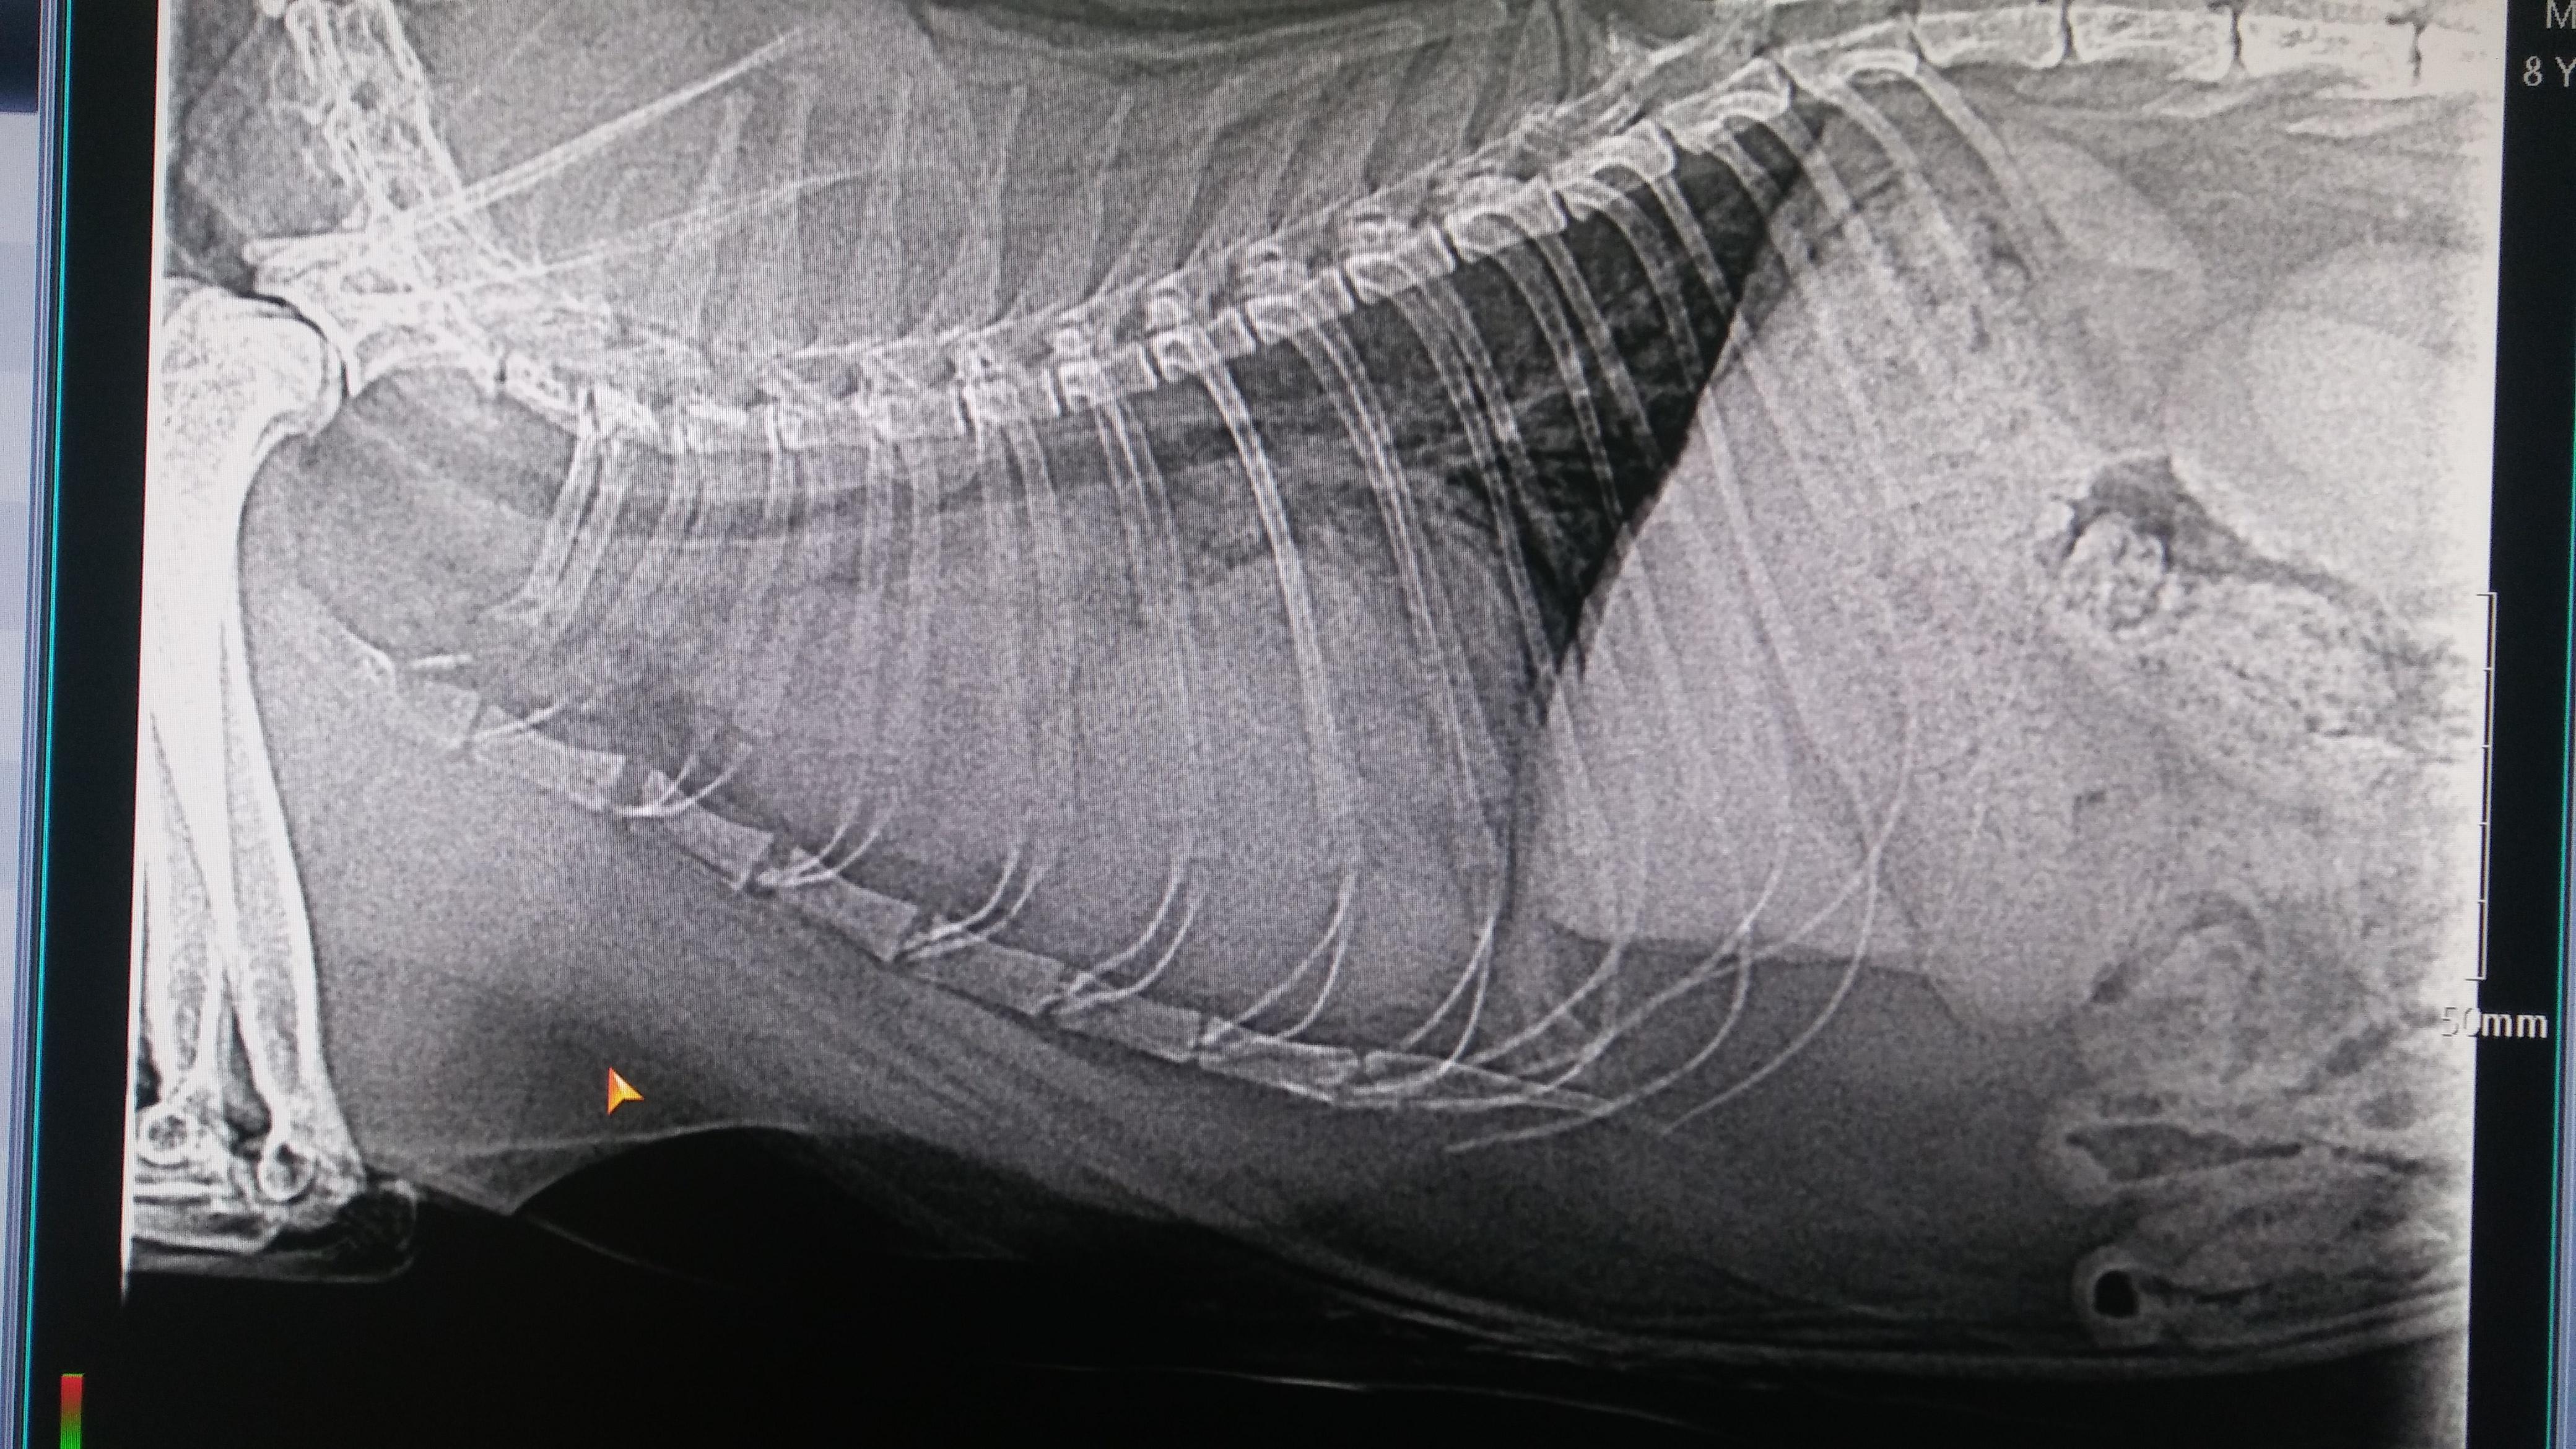

My cat has a very large mass between his chest and the vet doesnt know what it is do you have any idea what it may be

Oh dear! I'm sorry to hear that Bean is having this problem. Unfortunately, there is no way to diagnose what the mass is just by looking at it - he would need to have a biopsy or a fine needle aspirate (FNA) to get a sample of the tissue in the mass for analysis in order to get a specific diagnosis. In general, I can tell you that lymphoma is a common cause of a mass in this area in cats, but there's no way to know for sure if this is what Bean has without further work-up. For a mass or tumor in this area, I would normally recommend referral to a specialist for advanced imaging studies, biopsy or FNA, and discussion of treatment options. Your regular veterinarian should be able to help you set this up, if you wish.